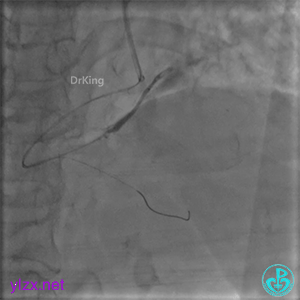

经微导管PL分支造影,该如何解读这个经微导管造影结果?

经指引导管造影。

经微导管造影。

远段造影剂外渗在增加,怎么办?